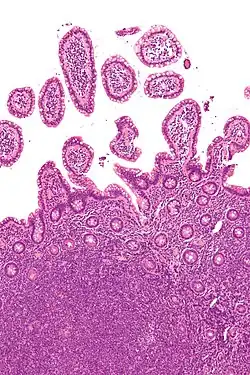

Micrograph of mantle cell lymphoma, a type of non-Hodgkin lymphoma. Terminal ileum. H&E stain.